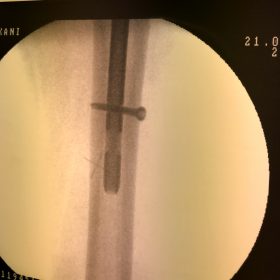

Υποκεφαλικό : Είναι ενδαρθρικό κάταγμα στον αυχένα του μηριαίου (το εσωτερικό του αρθρικού θυλάκου), το οποίο διακόπτει την αιμάτωση της κεφαλής του μηριαίου και οδηγεί σε μη πόρωση του κατάγματος (ΟΣΤΕΟΝΕΚΡΩΣΗ της Μηριαίας κεφαλής). Σε ασθενείς κάτω των 65 ετών αντιμετωπίζεται χειρουργικά με κοχλίωση στις πρώτες 12 ώρες. Τρείς βίδες σε σχήμα Τ με την βοήθεια τηλεόρασης διαδερμικά χωρίς διάνοιξη. Σε ασθενείς από 65-75 ετών γίνεται ολική αρθροπλαστική και σε ασθενείς άνω των 75 ετών αλλάζεται μόνο η κεφαλή χωρίς την αλλαγή της κοτύλης. Ο ασθενής περπατάει άμεσα μετεγχειρητικά στις 5 ώρες και εξέρχεται από το νοσοκομείο σε 1 -2 ημέρες. Στην κοχλίωση μπορεί να εξέλθει και την ίδια ημέρα.